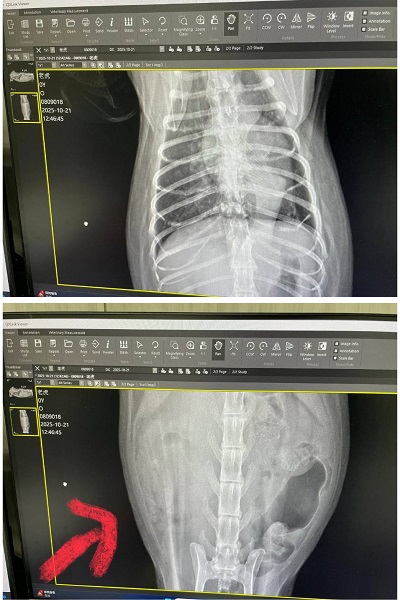

2025年6月2日回診的皮膚改善不夠理想、要更換黴菌藥,也還有些小顆粒要繼續刷洗,比較讓人擔心的是除了肝指數升高,紅血球及血容比持續下降,懷疑體內有其他地方在出血,因此在2025年6月16日回診的紅血球仍在下降及白血球也開始下降時,做超音波及X光檢查進一步查看,結果發現心臟尺寸較大,再加驗心臟快篩結果異常,且脾臟也有腫大、右腎上方有一個跟腎臟本身一樣大的腫瘤。

於2025年6月26日至專心醫院做心臟檢查,心臟尺寸較大快篩也呈陽性反應,並同時發現右腎有一個腫瘤,但因考量老虎年紀已大且身體狀況無法承受手術,所以還是決定以藥物進行治療。

2025年10月因老虎瞳孔放大精神狀況不佳而於同月21日回診,目前體重下降有些快但目前食慾精神還算穩定,還沒有出現症狀,右腎腫瘤過大問題採安寧照護,暫時也不需要回診,有食慾不好的狀況,可再回診拿類固醇跟止痛等藥物舒緩。若狀況持續變差則可向醫院領取嗎啡貼片及止痛藥。

至目前老虎的精神食慾尚可,但已來到末期的安寧照護,只希望盡可能讓老虎在最後階段能減緩身體的不適。本筆醫助是2025年6月26日於專心醫院及2025年6月30日至2025年10月21日間於沐恩醫院的費用,包含血檢、超音波、X光及用藥。

2025/6/26 老虎 專心 林正醫師

體重:5.75kg (6/16是5.8kg)

老虎於6/16至沐恩回診,X光檢查發現心臟尺寸比較大,心臟快篩也是陽性,且超音波檢查發現右腎有跟腎臟差不多大的腫瘤,腫瘤實際狀況需要CT才能確認,沐恩林院長建議先至心臟專科檢查心臟以確認是否可以進行CT跟手術,但協會顧慮,老虎的年紀及目前狀況可能無法承受手術,但就算最終決定不手術,也可以看醫生建議是否需要服用心臟藥物。

心電圖檢查及心臟超音波檢查都沒有發現異常,心臟尺寸大小也正常。

2025/10/21 老虎 沐恩 林院長

體重:4.435kg (6/30是5.61kg)

請醫師協助剪指甲。體重掉稍微比較多,腫瘤引起比較有關係

皮膚跟體力有影響關係,右腎腫瘤過大只做安寧照護就先維持

胸有點不明物體不確定是什麼物體(也有可能是瘦太快皮膚皺摺陰影),有明顯的呼吸聲,也不像肺部轉移物質,超音波檢查是沒事。